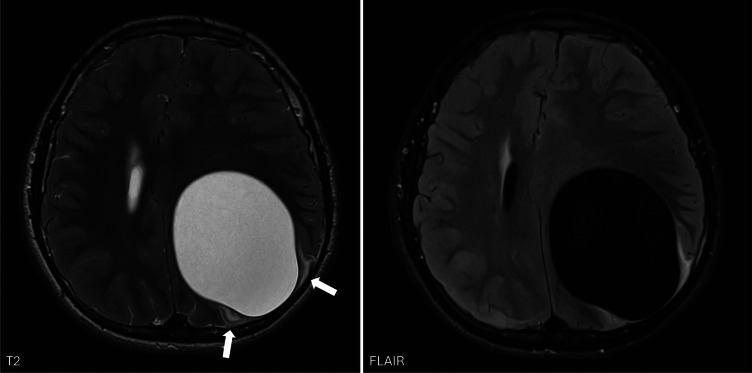

教学要点:当怀疑有脑包虫病时,需要胸腹影像学检查颅内外病变。当发现无并发症的轴内囊肿时,应鉴别诊断包虫病,特别是来自或有流行地区旅行史的患者,或已知接触过狗、羊或牛的患者。胸腹影像可能有助于诊断,因为包虫病更常累及肝脏和肺部,很少累及大脑。

Teaching point: When hydatid disease in the brain is suspected, thoraco-abdominal imaging is warranted to detect extracranial lesions. When an uncomplicated intra-axial cyst is encountered, hydatid disease should be in differential diagnosis, especially in patients from or with travel history to endemic areas, or with known exposure to dogs, sheep or cattle. Thoraco-abdominal imaging may aid diagnosis as hydatid disease more commonly affects the liver and lungs and only rarely the brain.